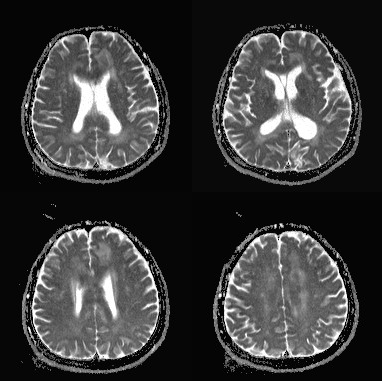

影像资料:

•急性期表现为胼胝体弥漫性肿胀,T1WI呈稍低信号,T2WI及FLAIR呈稍高信号,以矢状位观察最佳,可单独累及胼胝体压部或整个胼胝体,DWI呈高信号,ADC图呈低信号,部分患者可观察到脑室周围白质或内囊受累,少见皮层受累,表现为扩散受限,不强化和强化病例均可见到。如果增强扫描可见胼胝体有不同程度强化,呈小灶状或不规则斑片状,系血脑屏障破坏所致(如本例),本例患者处于急性期。 医学百科网 | YxBaike.Com

上排:原发性胼胝体变性急性期

下排:原发性胼胝体变性慢性期,表现为胼胝体萎缩、软化